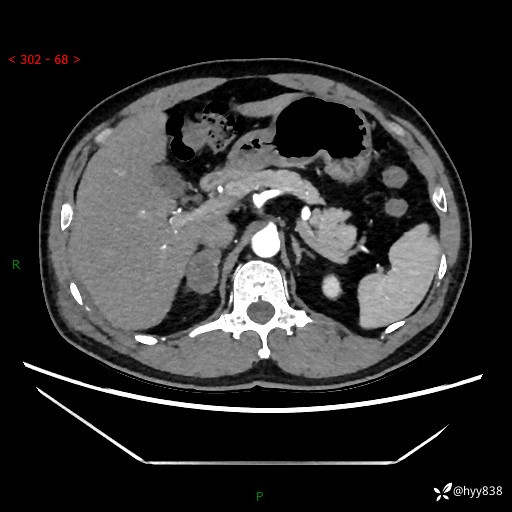

现病史:患者9月4日摔伤在深圳市宝安区中心医院行CT检查提示右侧肾上腺区结节(38*27mm),复查B超提示右侧肾上腺区可见一61*24mm异常低回声团,建议进一步检查。进一步完善增强CT后提示:右侧肾上腺区肿块及周围渗出改变,大致同前,考虑肾上腺腺瘤,不除外瘤内出血可能,否认阵发性头晕、头痛、出汗、乏力等不适,门诊以“ 右侧肾上腺肿瘤”收入住院。 起病来,患者精神、食欲、睡眠可,大便通畅,小便如上述,体力体重无明显改变。

肾上腺CT平扫

增强(动脉期+静脉期)

单侧肾上腺病变,鉴别诊断有哪些